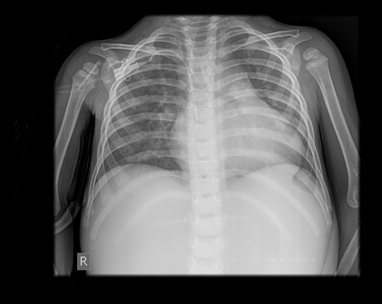

Figure 2 X ray-bronchovascular drawing emphasized right hiloperihilar and paracardiobasal with a field of plate-like small atelectasis.

Postoperative course: The patient was transferred to ICU within stable hemodynamic findings with moderate inotropic support. The patient was extubated an early after operation and transferred to the patient floor on the first postoperative day. No microorganism was isolated in the tissue culture sent during the operation. Antibiotic treatment was continued for two weeks postoperatively. The last post-ICU follow-up was uneventful and the last chest X-ray and laboratory findings were within normal limits.